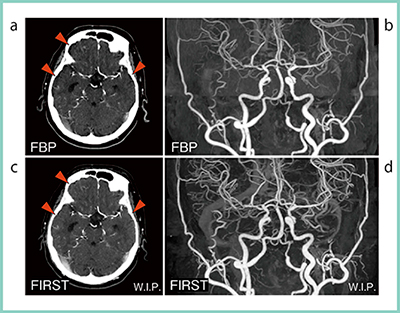

FIRST Brain CTA は分解能に特化したパラメータである(図7 c,d)。高いBHC効果があり,カッピングアーチファクトを除去するとともに,MIP画像では末梢血管をより明瞭に描出することができる。

図7 CTAの臨床画像